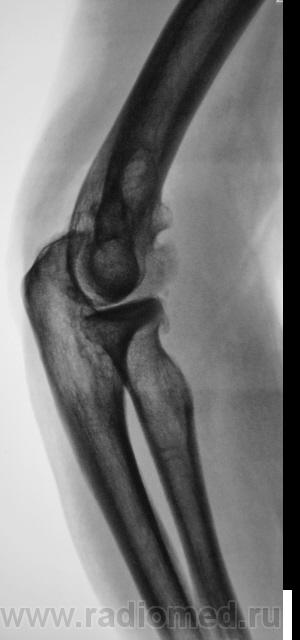

Пациент направлен на рентгенографию локтевого сустава. Была травма или не была не помнит. Пациент весьма пьющий, направлен хирургом с диагнозом "перелом". Рука в локтевом суставе полность не разгибается.

Ваше мнение уважаемые коллеги?

Наверно, застарелый перелом в области блока плечевой кости. Не понятен периостит.